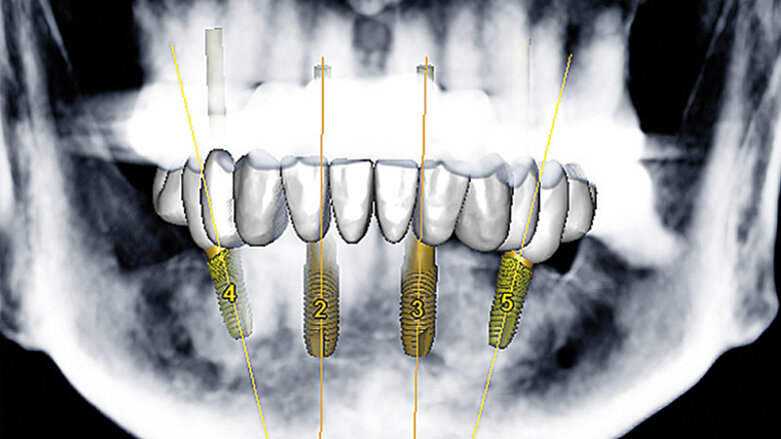

Následovalo plánování založené na počítačové tomografii (CBCT), zbývající mandibulární zuby pacientky byly extrahovány. Bylo provedeno plánování léčby implantáty v softwaru SimPlant (Dentsply Sirona Implants), který ukázal vhodnou polohu zubů a odhadovanou polohu frontálních implantátů (OsseoSpeed EV) a distálních implantátů (OsseoSpeed Profile EV) v mezích navrhované finální náhrady (obr. 3).

Obr. 3: Plánování implantace prováděné pomocí softwaru SimPlant (Dentsply Sirona Implants)